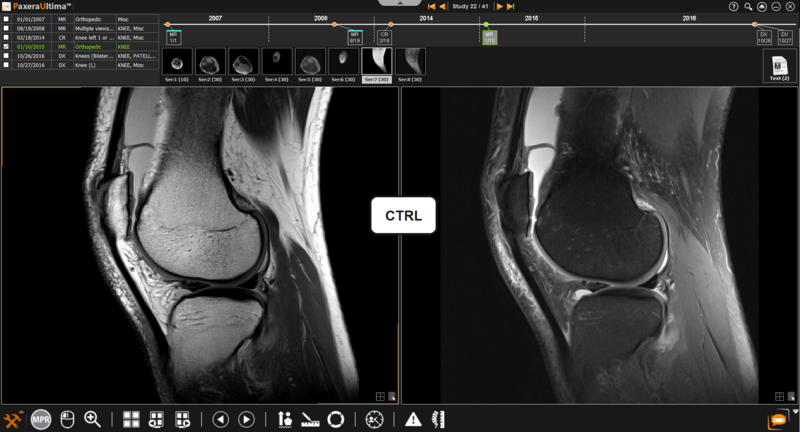

1.          Select the two series that you would like to link by holding down the 'Ctrl" key and clicking on the series. Selected series will be outlined with a white box.

An infinity sign will be shown on the top of each image window to indicate that both series are linked.